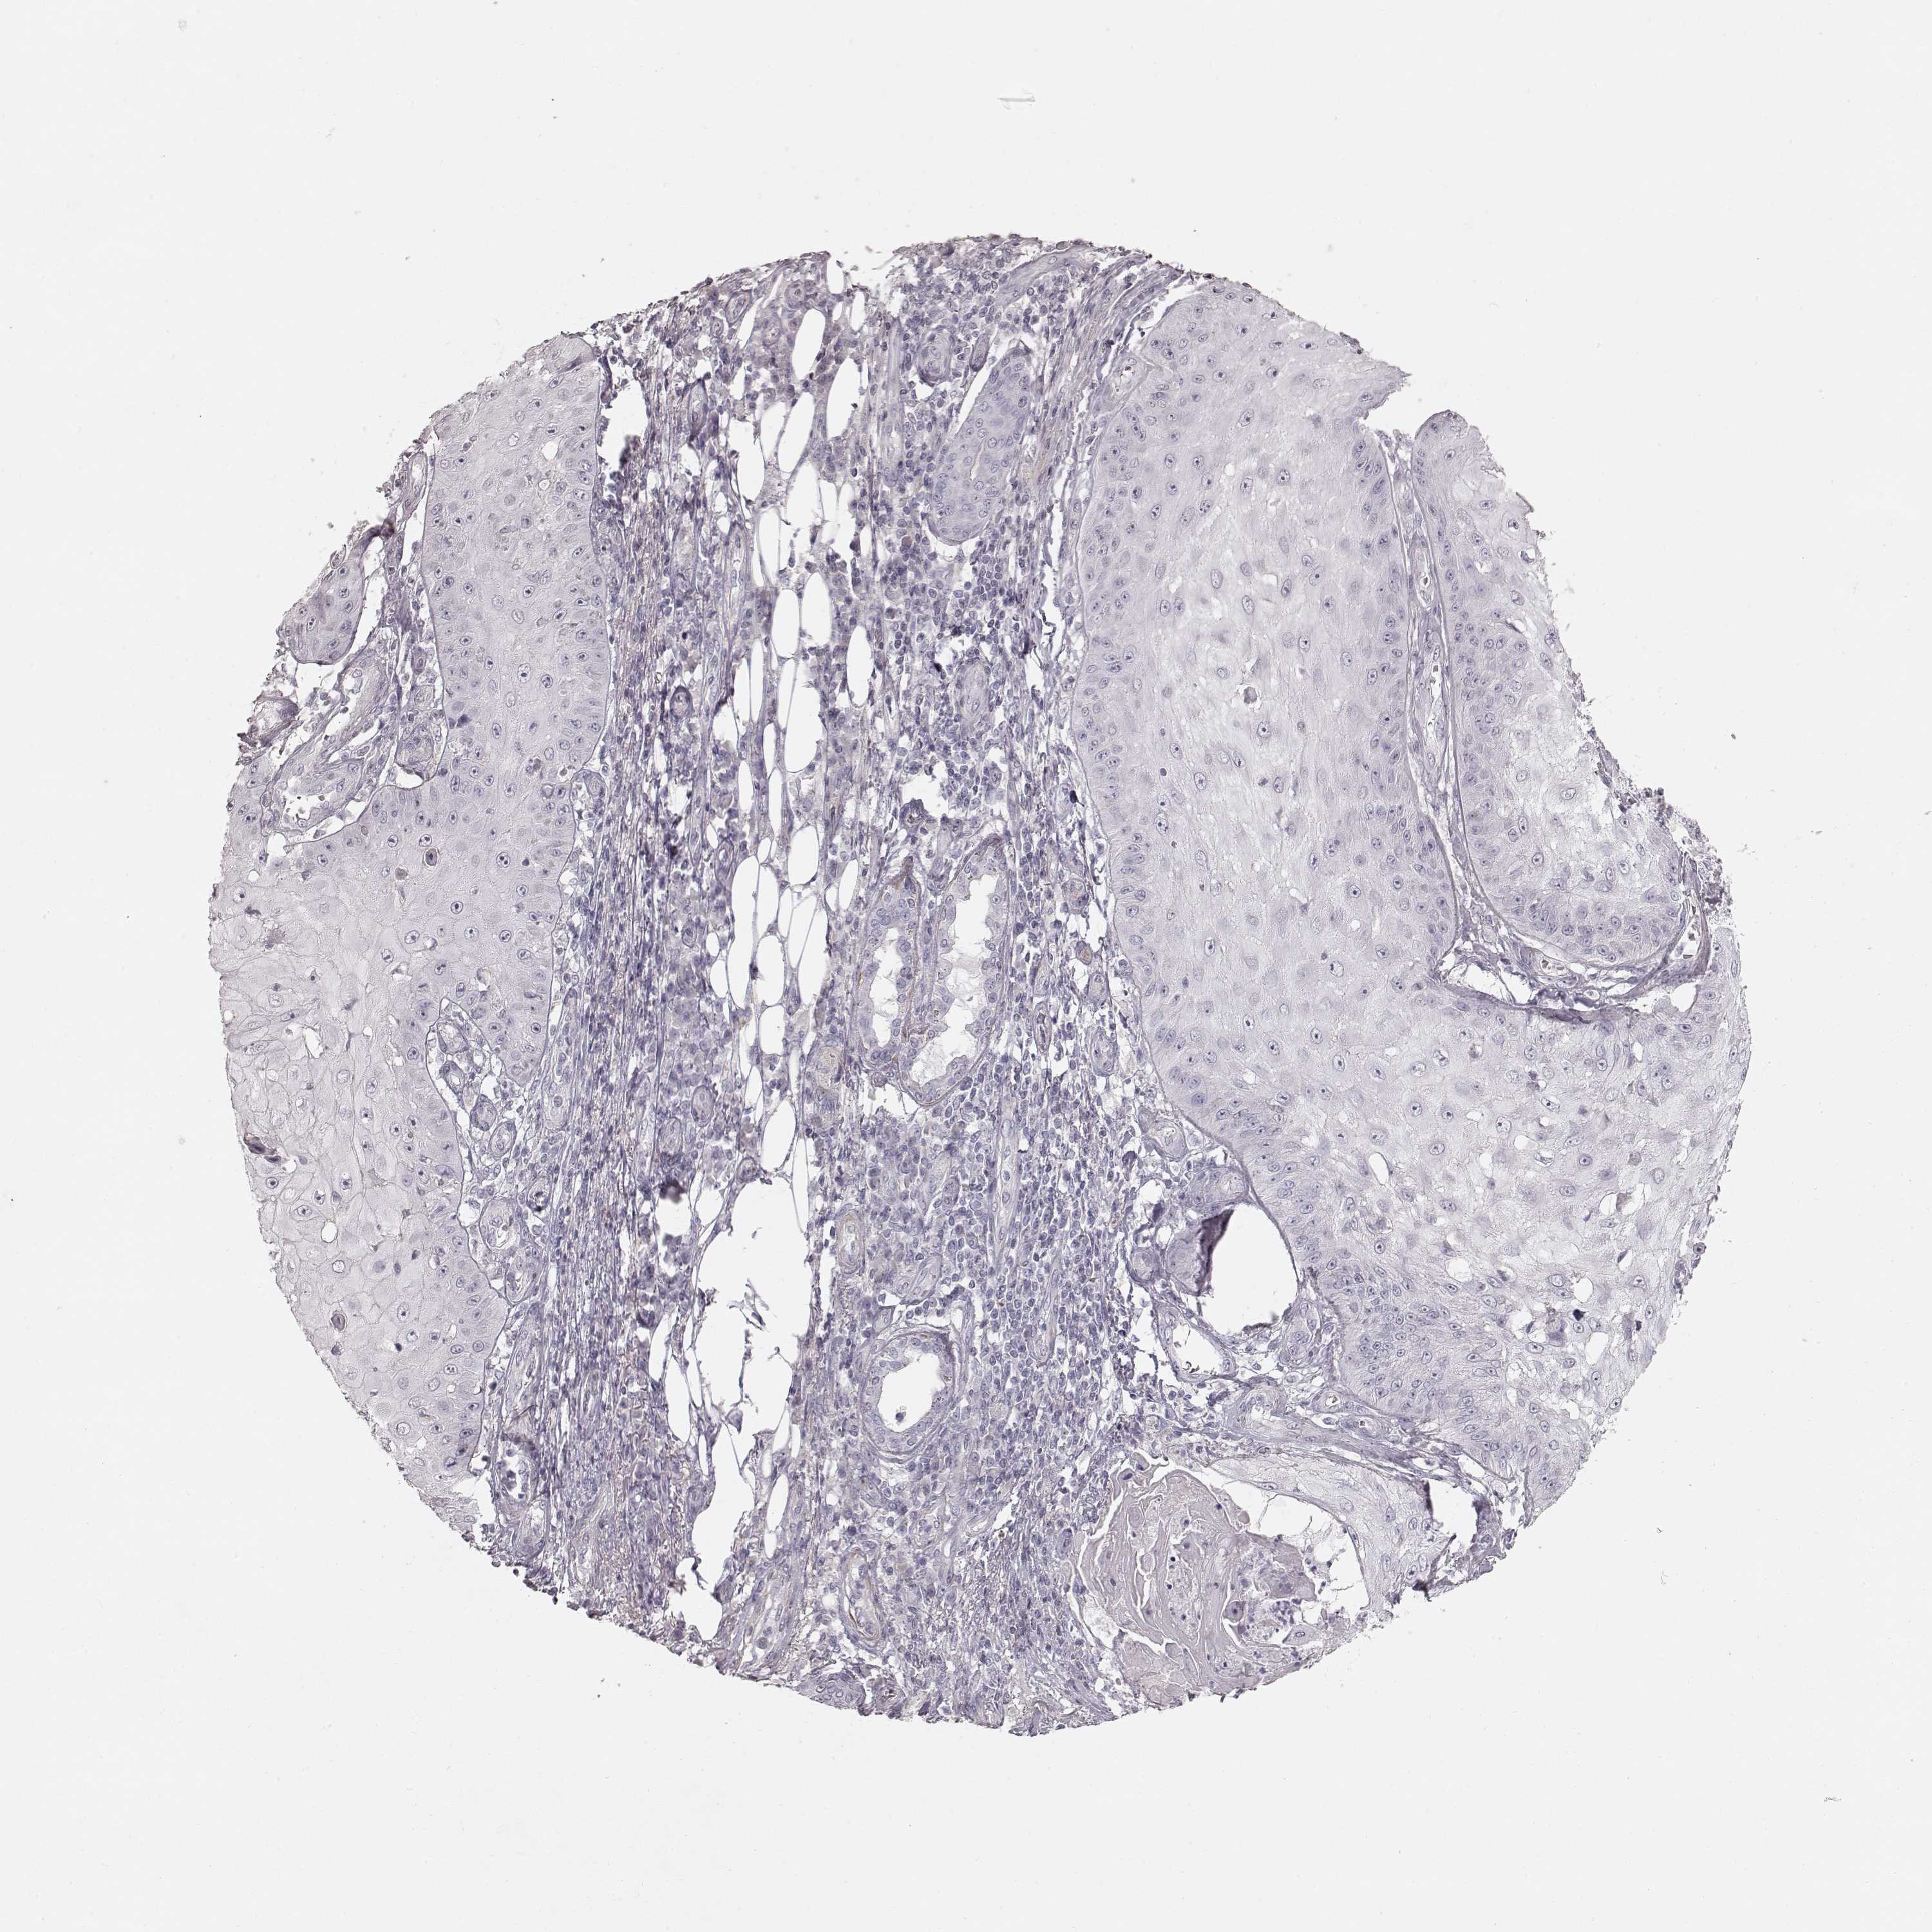

Basal cell and squamous cell cancer

SKIN CANCER - Protein expressioni

A mouse-over function shows sample information and annotation data. Click on an image to view it in a full screen mode. Samples can be filtered based on level of antibody staining by selecting one or several of the following categories: high, medium, low and not detected. The assay and annotation is described here.

Antibody stainingi

Antibody staining in the annotated cell types in the current human tissue is reported as not detected, low, medium, or high, based on conventional immunohistochemistry profiling in selected tissues. This score is based on the combination of the staining intensity and fraction of stained cells.

Each image is clickable and will lead to virtual microscopy that enables deeper exploration of all samples and also displays staining intensity scores, fraction scores and subcellular localization as well as patient and tissue information for each sample.

Antibody HPA039361

Basal cell carcinoma

Squamous cell carcinoma, NOS